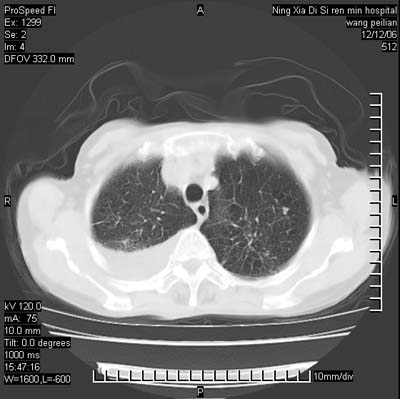

标题: CT5609:胸部:女77 病史不详 [打印本页]

标题: CT5609:胸部:女77 病史不详

两肺可见多个大小不等的结节,左侧有胸水,纵隔淋巴结增大,考虑是细支气管肺泡癌

两肺尖纤维索状影,两下肺结节块状影,且有钙化灶,右胸腔积液。考虑肺结核并胸膜炎。

双侧肺结核伴右侧胸腔积液.

两肺尖纤维索状影,两下肺结节块状影,且有钙化灶,右胸腔积液。考虑肺结核并胸膜炎肺间质纤维化

考虑:1、慢性支气管炎合并全小叶型肺气肿、间质纤维化;

2、双肺结核;

3、右侧胸膜炎(积液)。

1、双肺继发型肺结核(以纤维、增殖灶为主);

2、右侧胸腔积液;

3、其余符合老年肺改变。

双肺见多个结节状及条索状影,双侧胸腔积液,右侧叶间积液,考虑结核性胸膜炎

肺结核并右侧结核性胸膜炎